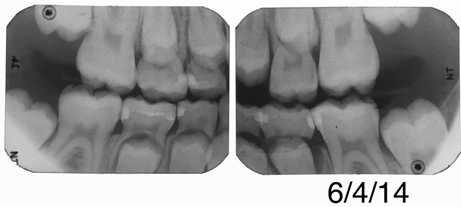

Fig 13. Bitewing of a 7-year-old girl. F

Figure 13

Fig 14. Same patient more than 3 years later.

Figure 14

Fig 15. Bitewing of an 11-year-old boy.

Figure 15

Fig 16. Same patient several months later.

Figure 16

Figure 13 shows a bitewing of a 7-year-old girl with Williams syndrome who had previously required treatment under general anesthesia (GA) in a hospital setting for treatment of caries in her primary teeth. An incipient lesion on the mesial of her lower right permanent first molar, tooth No. 30, was treated more conservatively, in office, with resin infiltration, which allowed her to avoid more invasive treatment and the possible need for another GA. The lesion was arrested (Figure 14) and has been stable for over 5 years.

Figure 15 shows bitewings of an 11-year-old boy with high caries risk and history of proximal "kissing lesions" on his primary molars in all four quadrants. He then presented with incipient lesions in his permanent teeth. After resin infiltration (Figure 16), results have been stable for 2 years.